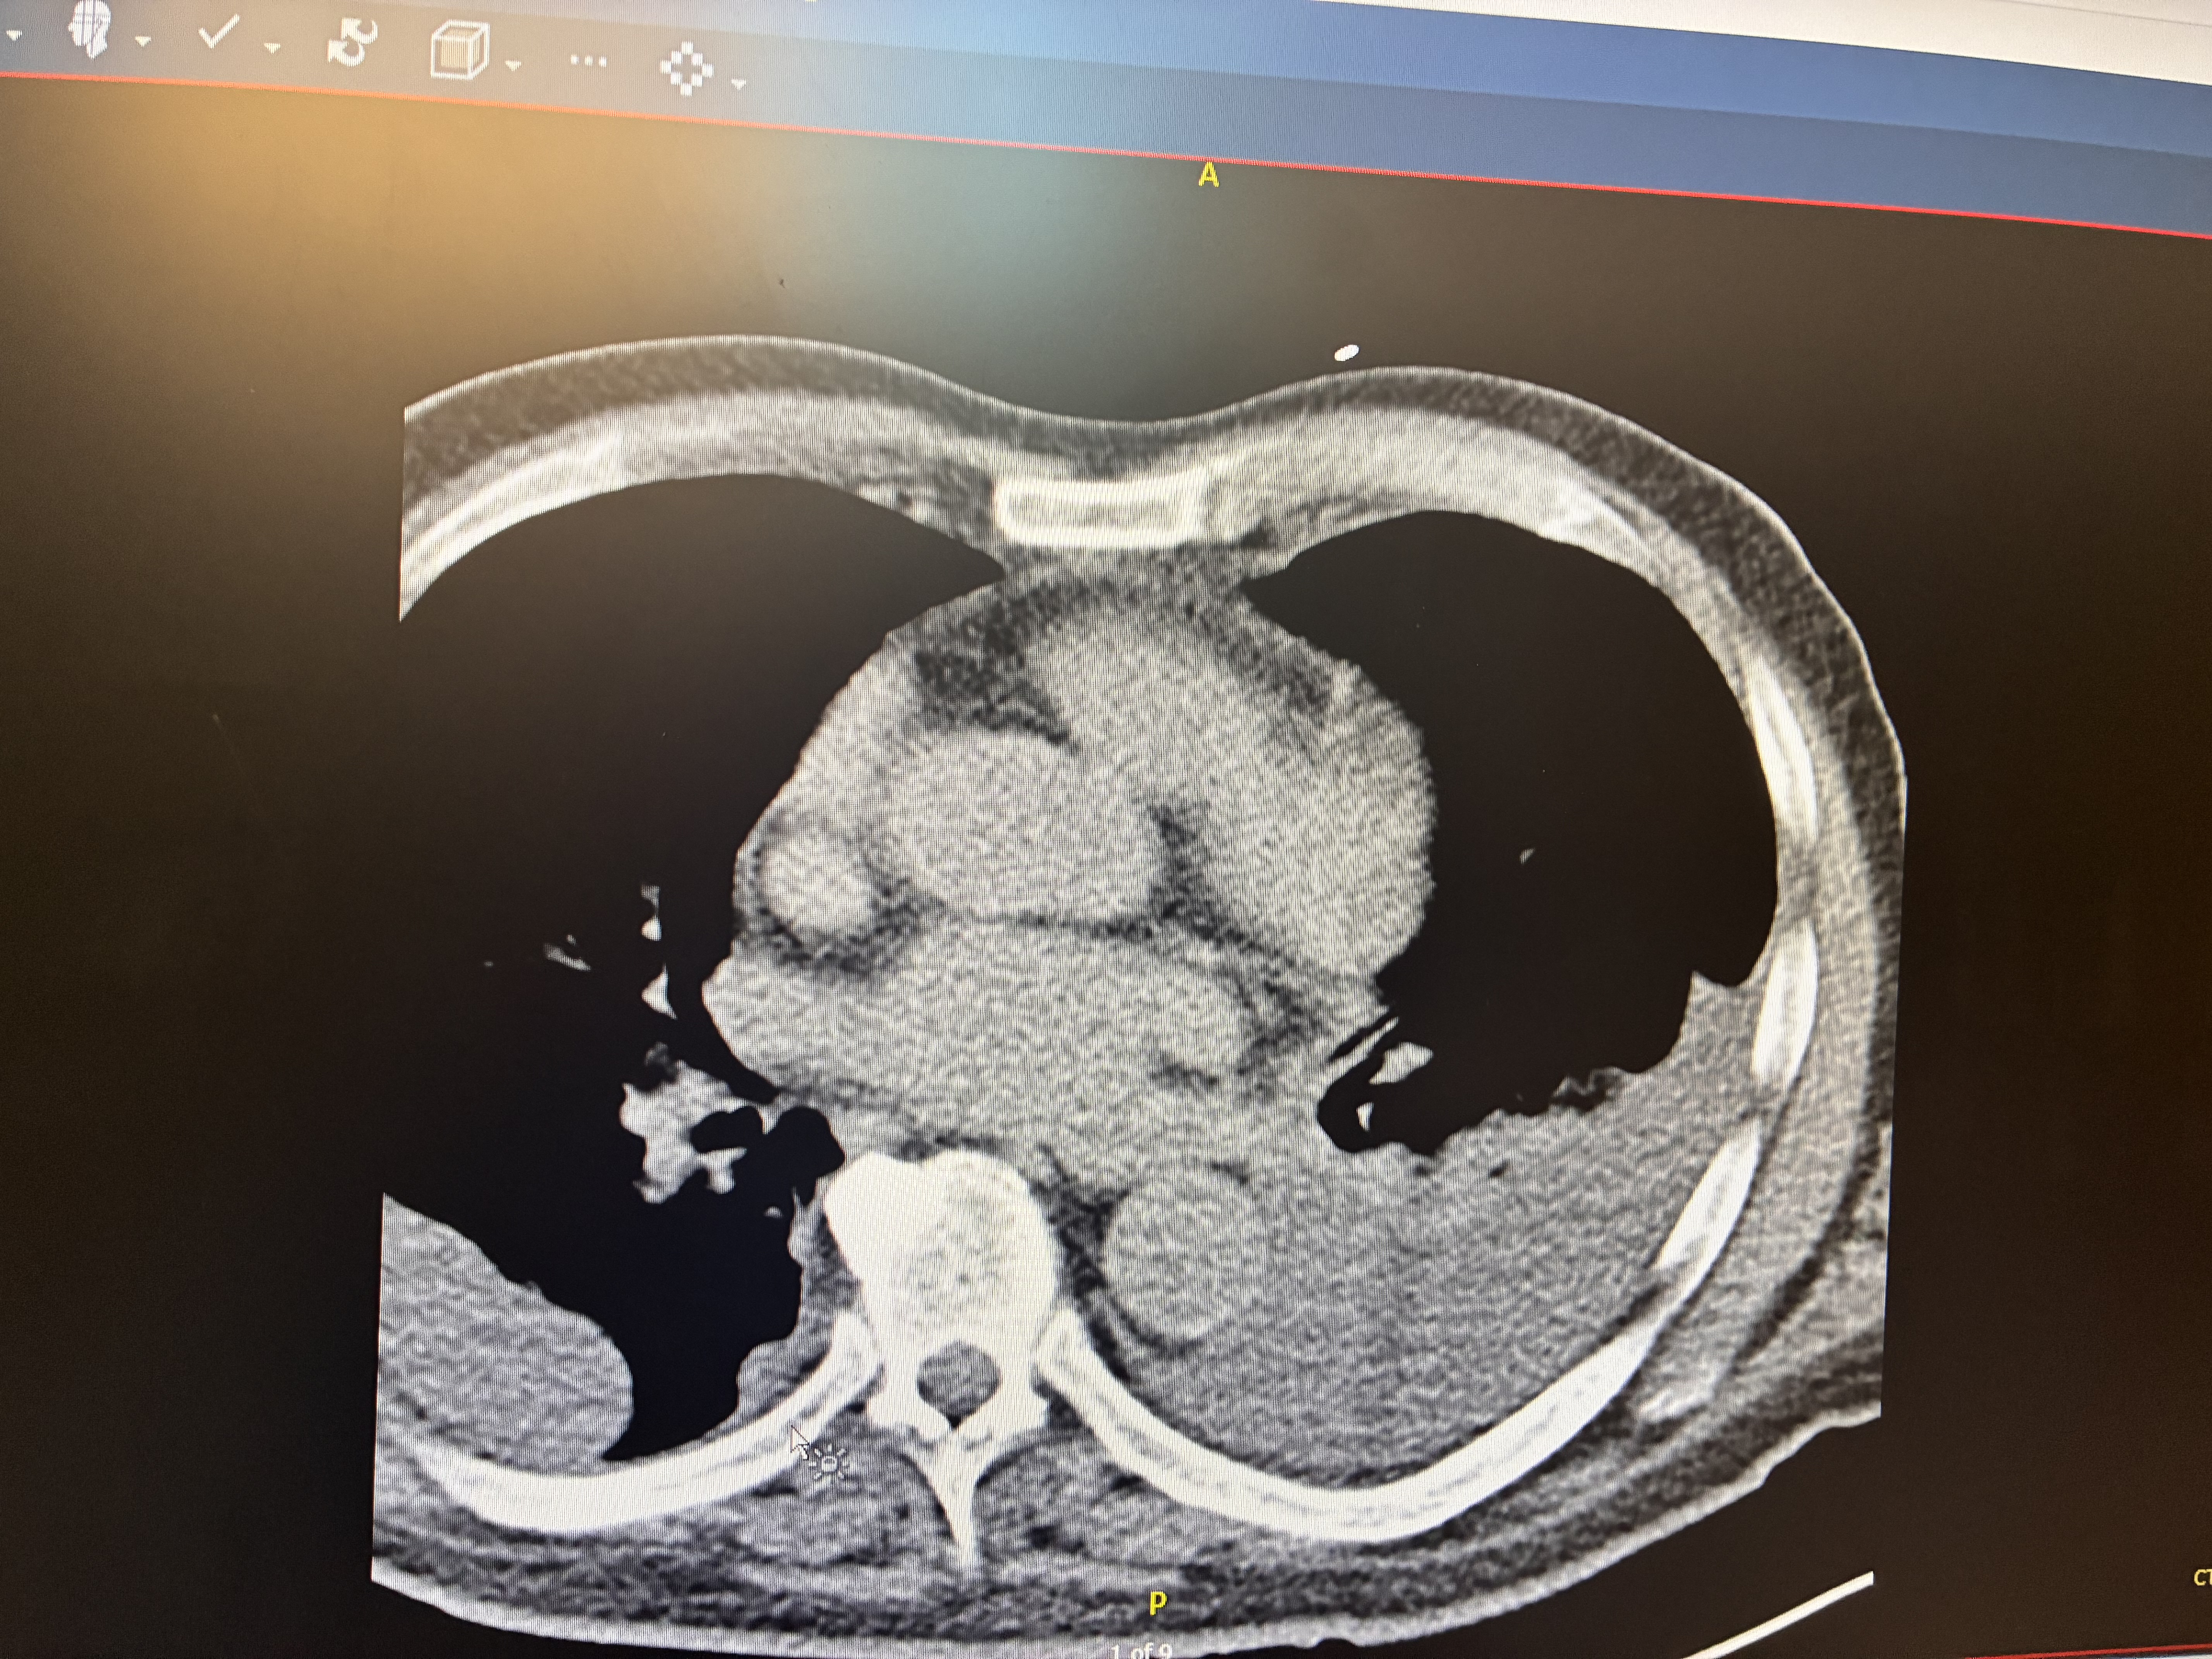

I am immediately put back into Emergency and the next day have an operation to suck fluids out of my lungs.